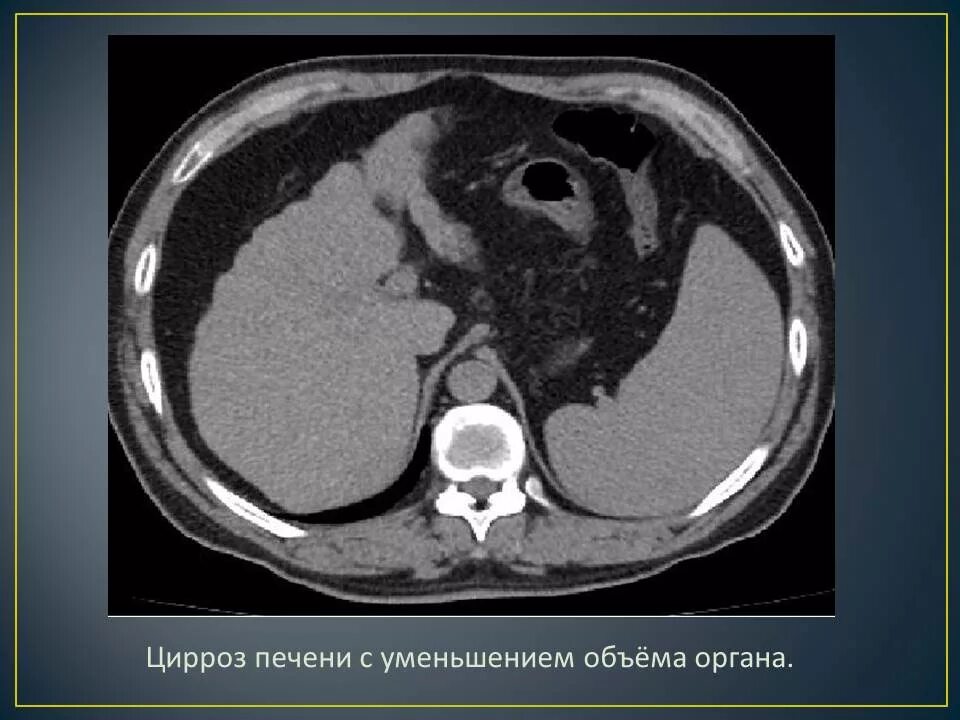

Цирроз на кт